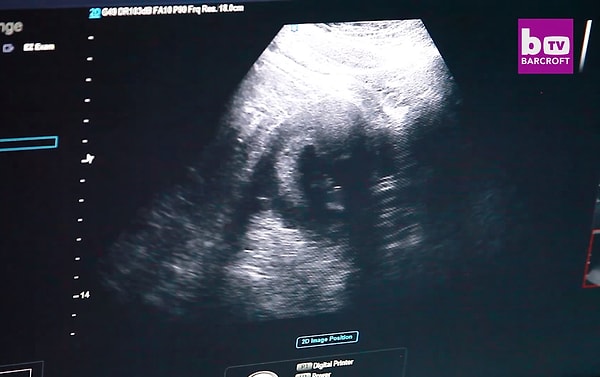

Сейчас Моника на 15 неделе беременности.

Для того, чтобы родить здорового ребенка, Моника уже похудела на 91 кг всего за 10 недель. Сейчас она весит 226 кг.